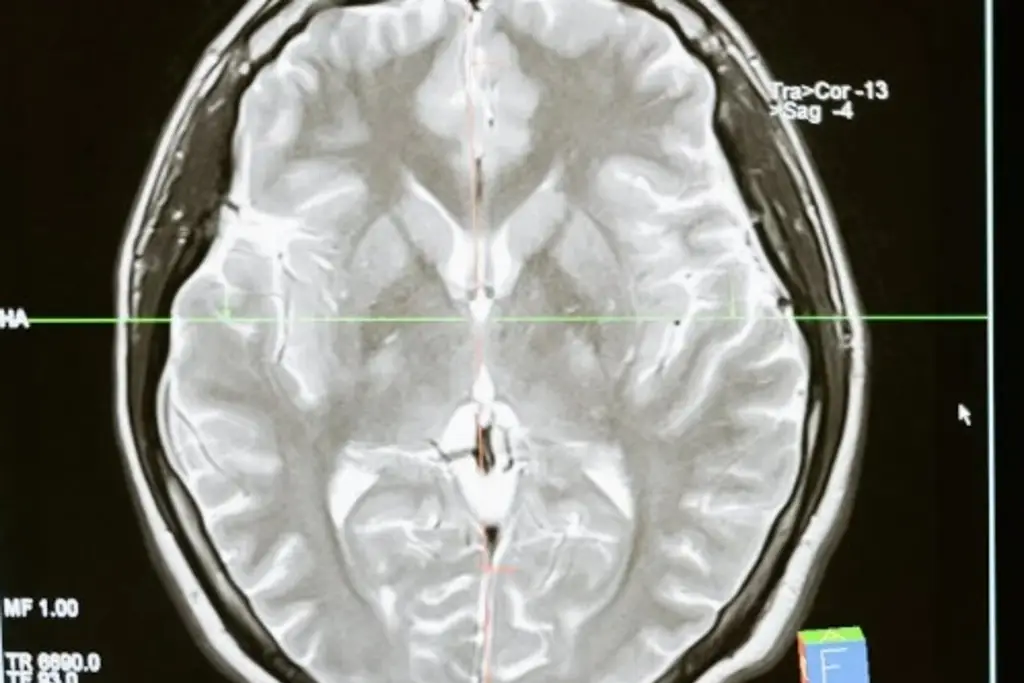

Crean células capaces de eliminar uno de los peores tumores cerebrales

Un equipo de investigación de la Universidad de Ginebra (UNIGE) anunció este jueves que ha logrado crear células inmunitarias que reconocen y eliminan las pertenecientes al glioblastoma, un cáncer cerebral extremadamente agresivo y con muy bajas tasas de supervivencia.

El glioblastoma es un cáncer extremadamente resistente a la inmunoterapia, y con una tasa de supervivencia menor al 5 % cinco años después de su desarrollo.